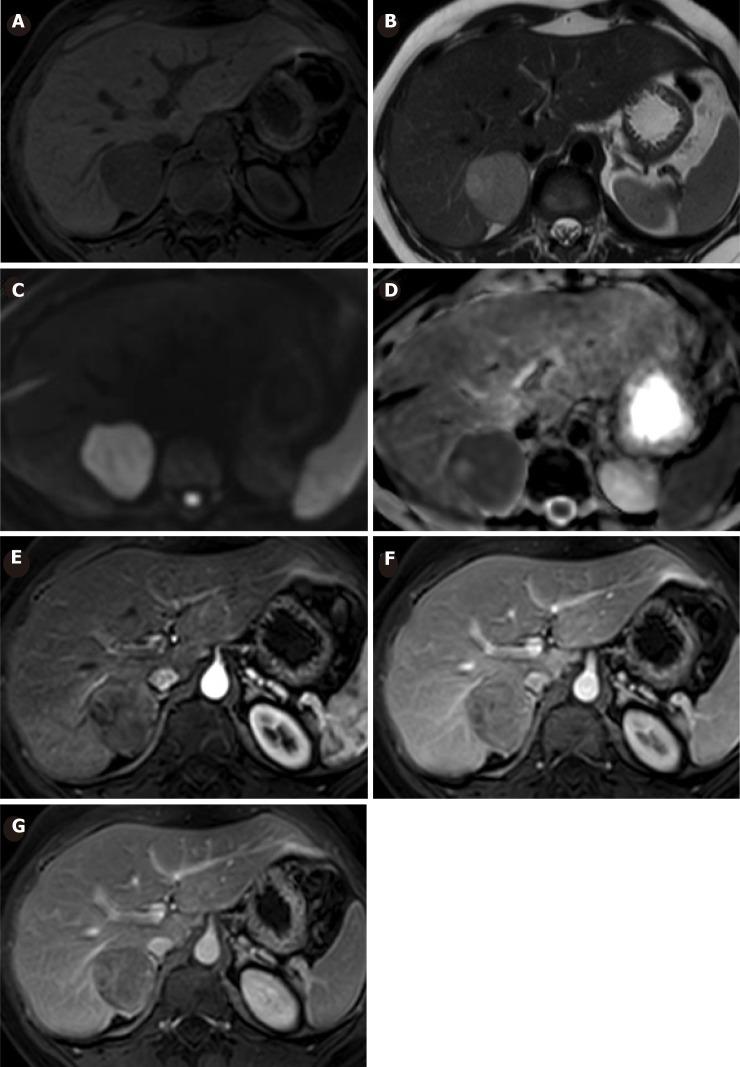

A 33-year-old female with a 10-year history of oral contraceptive use was diagnosed with a hepatic tumor as an incidental finding in an abdominal ultrasound. The patient showed no symptoms and physical examination was unremarkable. Laboratory functional tests were within normal limits and tests for serum tumor markers were negative. An abdominal magnetic resonance imaging (MRI) was performed, showing a 30 mm × 29 mm focal lesion in segment VI of the liver compatible with HCA or Focal Nodular Hyperplasia with atypical behavior. After a total of six years of follow-up, the patient underwent ovulation induction treatment for infertility. On a following MRI, a suspected malignancy was warned and hence, surgery was decided. The surgical specimen revealed malignant transformation of HCA towards trabecular hepatocarcinoma with dedifferentiated areas. There was non-evidence of tumor recurrence after three years of clinical and imaging follow-up.

一名有10年口服避孕药史的33岁女性,在腹部超声检查中偶然发现肝脏肿瘤。患者无症状,体格检查无异常。实验室功能检查在正常范围内,血清肿瘤标志物检测为阴性。进行了腹部磁共振成像(MRI)检查,显示肝脏VI段有一个30mm×29mm的局灶性病变,符合HCA或具有非典型表现的局灶性结节性增生。经过总共6年的随访,患者因不孕症接受了促排卵治疗。在随后的MRI检查中,发现疑似恶变,因此决定进行手术。手术标本显示HCA向小梁状肝细胞癌伴去分化区域恶变。经过3年的临床和影像学随访,未发现肿瘤复发迹象。